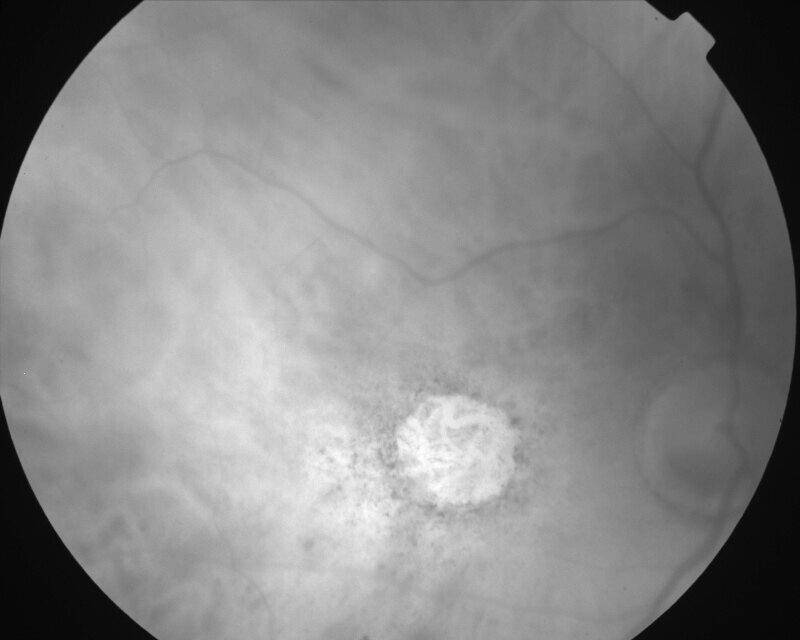

ATROPHIE AREOLAIRE CENTRALE